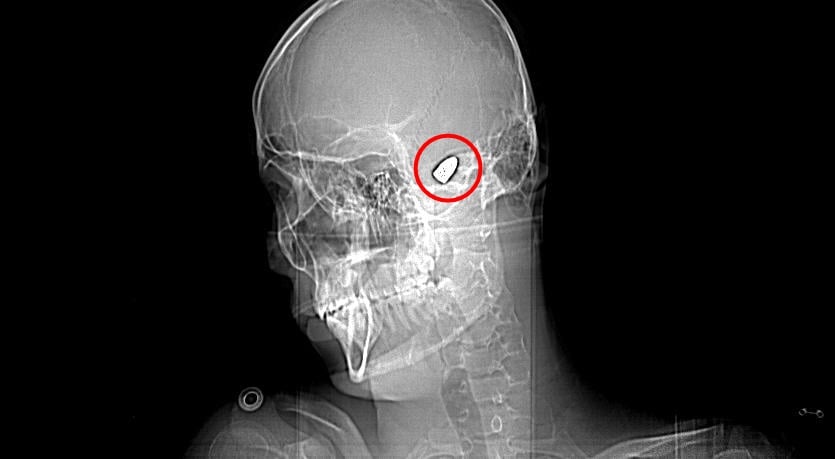

Çevredekilerin hastaneye götürdüğü Yusuf’un çekilen röntgeninde, başında mermi çekirdeği olduğu tespit edildi.

Doktorlar Yusuf’un başındaki merminin riskli bir bölgede olması sebebiyle çıkarılamayacağını söyledi. 4 gün yoğun bakım, 4 gün de serviste tedavi gören Yusuf düzenli olarak doktor kontrollerine gitti.